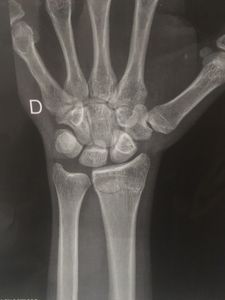

No dia 4 de novembro me acidentei na avenida do estado, estava voltando de uma entrega no centro de São Paulo quando um carro me fechou, pra não bater nele eu desviei e acabei batendo atrás de um caminhão a mais ou menos 70km/h.

Quebrei o braço na região do pulso e fiquei 45 dias imobilizado, comecei a vender alfajor pra levantar algum dinheiro, fui em alguns amigos recorrer ajuda pra comer, não fiquei parado. Mas não é fácil. Perto do final do ano isso acabou atrasando várias contas e o dinheiro que eu tinha pro DOC da moto, acabou virando remédio e comida. Dependo da moto pra poder pagar minhas contas e não tenho condições de arrumar ela, qualquer ajuda é bem vinda.